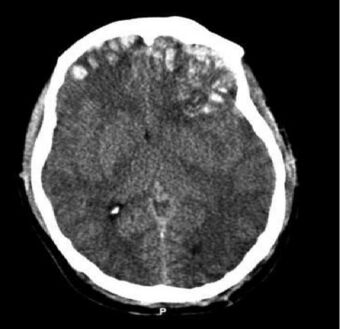

Brain trauma CT.jpg

CT scan showing cerebral contusions, hemorrhage within the hemispheres, and subdural hematoma. There is also displaced skull fracture of left transverse parietal and temporal bones.[2]